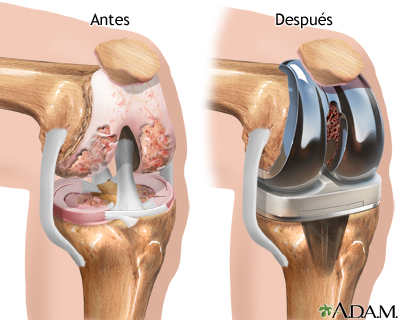

Esta opción está pensada principalmente para quienes presentan desgaste severo de la articulación, dolor persistente o limitaciones importantes para caminar y realizar actividades cotidianas.

A diferencia del procedimiento tradicional, el sistema robótico permite realizar cortes más precisos en el hueso mediante un software que guía al cirujano en tiempo real.

Esto ayuda a colocar los implantes con mayor exactitud y a lograr una alineación personalizada, ajustada a la anatomía de cada paciente.